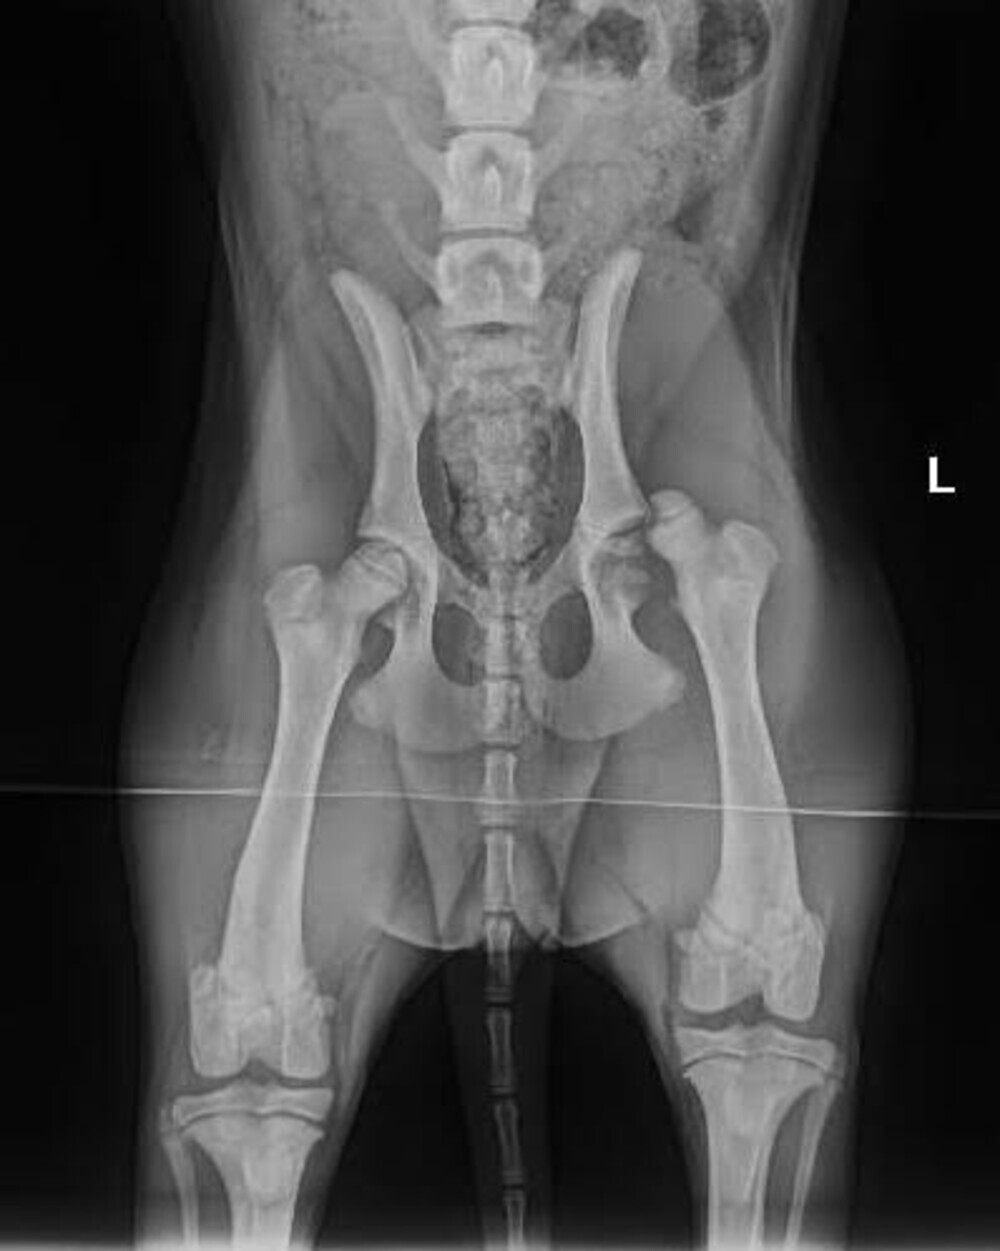

22 april: Ellis Coco heeft deze week controle bij de dierenarts gehad en de conclusie is dat ze erg goed hersteld: lopen mag weer uitgebreid en zonder verdere complicaties hoeft ze niet meer terug.

Gevolg; heup uit de kom en een stukje afgebroken vd kop van de femur.

Op aandringen van ons (eerst dachten ze dat het alleen gekneusd was) en de dierenarts zijn er foto’s gemaakt en is ze gisteren onder het mes gegaan en is er een nieuwe kop geplaatst.

29 maart: Ellis Coco vandaag weer langs de dierenarts en het herstel gaat goed, voldoende rust blijft de key, iets waar Ellis Coco nog wel moeite mee heeft: laatste gewicht 12,2 kg.